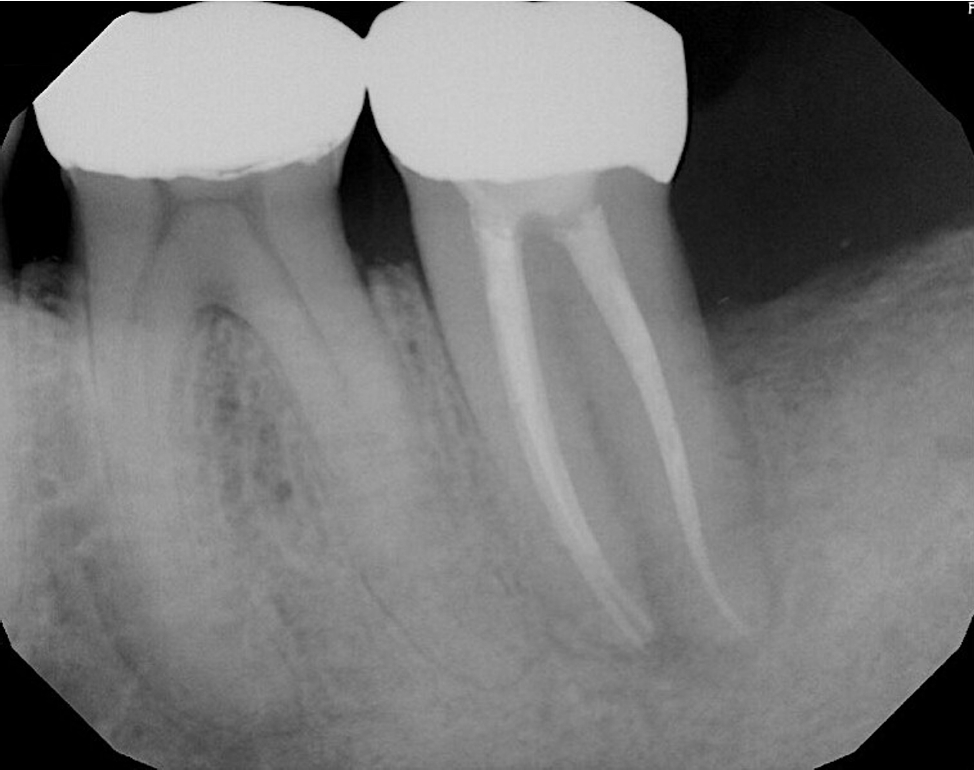

Radiographically, a “J-shaped” lesion was observed along the distal root of #18 (Figure 1), suggestive of a primary endodontic lesion with secondary periodontal involvement. A radiopaque fragment, consistent with a cemental tear, was identified along the distal root surface (Figure 1).

Figure 1.

“J-shaped” lesion observed along the distal root of #18 (yellow arrow). A radiopaque fragment, consistent with a cemental tear, was identified along the distal root surface (red arrow).

rde-2025-50-e31f1.jpg

Figure 1. “J-shaped” lesion observed along the distal root of #18 (yellow arrow). A radiopaque fragment, consistent with a cemental tear, was identified along the distal root surface (red arrow).